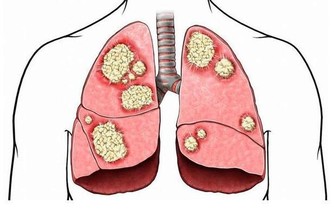

據報導,全球胃癌患者有一半在中國,除了眾所周知的幽門螺桿菌以外,還有一個致癌因素常常被國人所忽視。經過大範圍的調研發現,許多患有胃癌或者食管癌的患者都喜歡吃燙食,這個結果並非偶然。